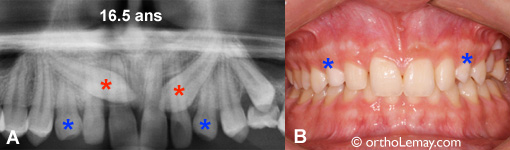

16.5 ans

Chez cette fille de 16 ans, les canines permanentes (* rouges) sont presque complètement vers le centre (et au palais). Cette situation était visible il y a plus de 7-8 ans et l’extraction des canines temporaires aurait certainement aidé la situation, sans “garantir” une éruption normale.